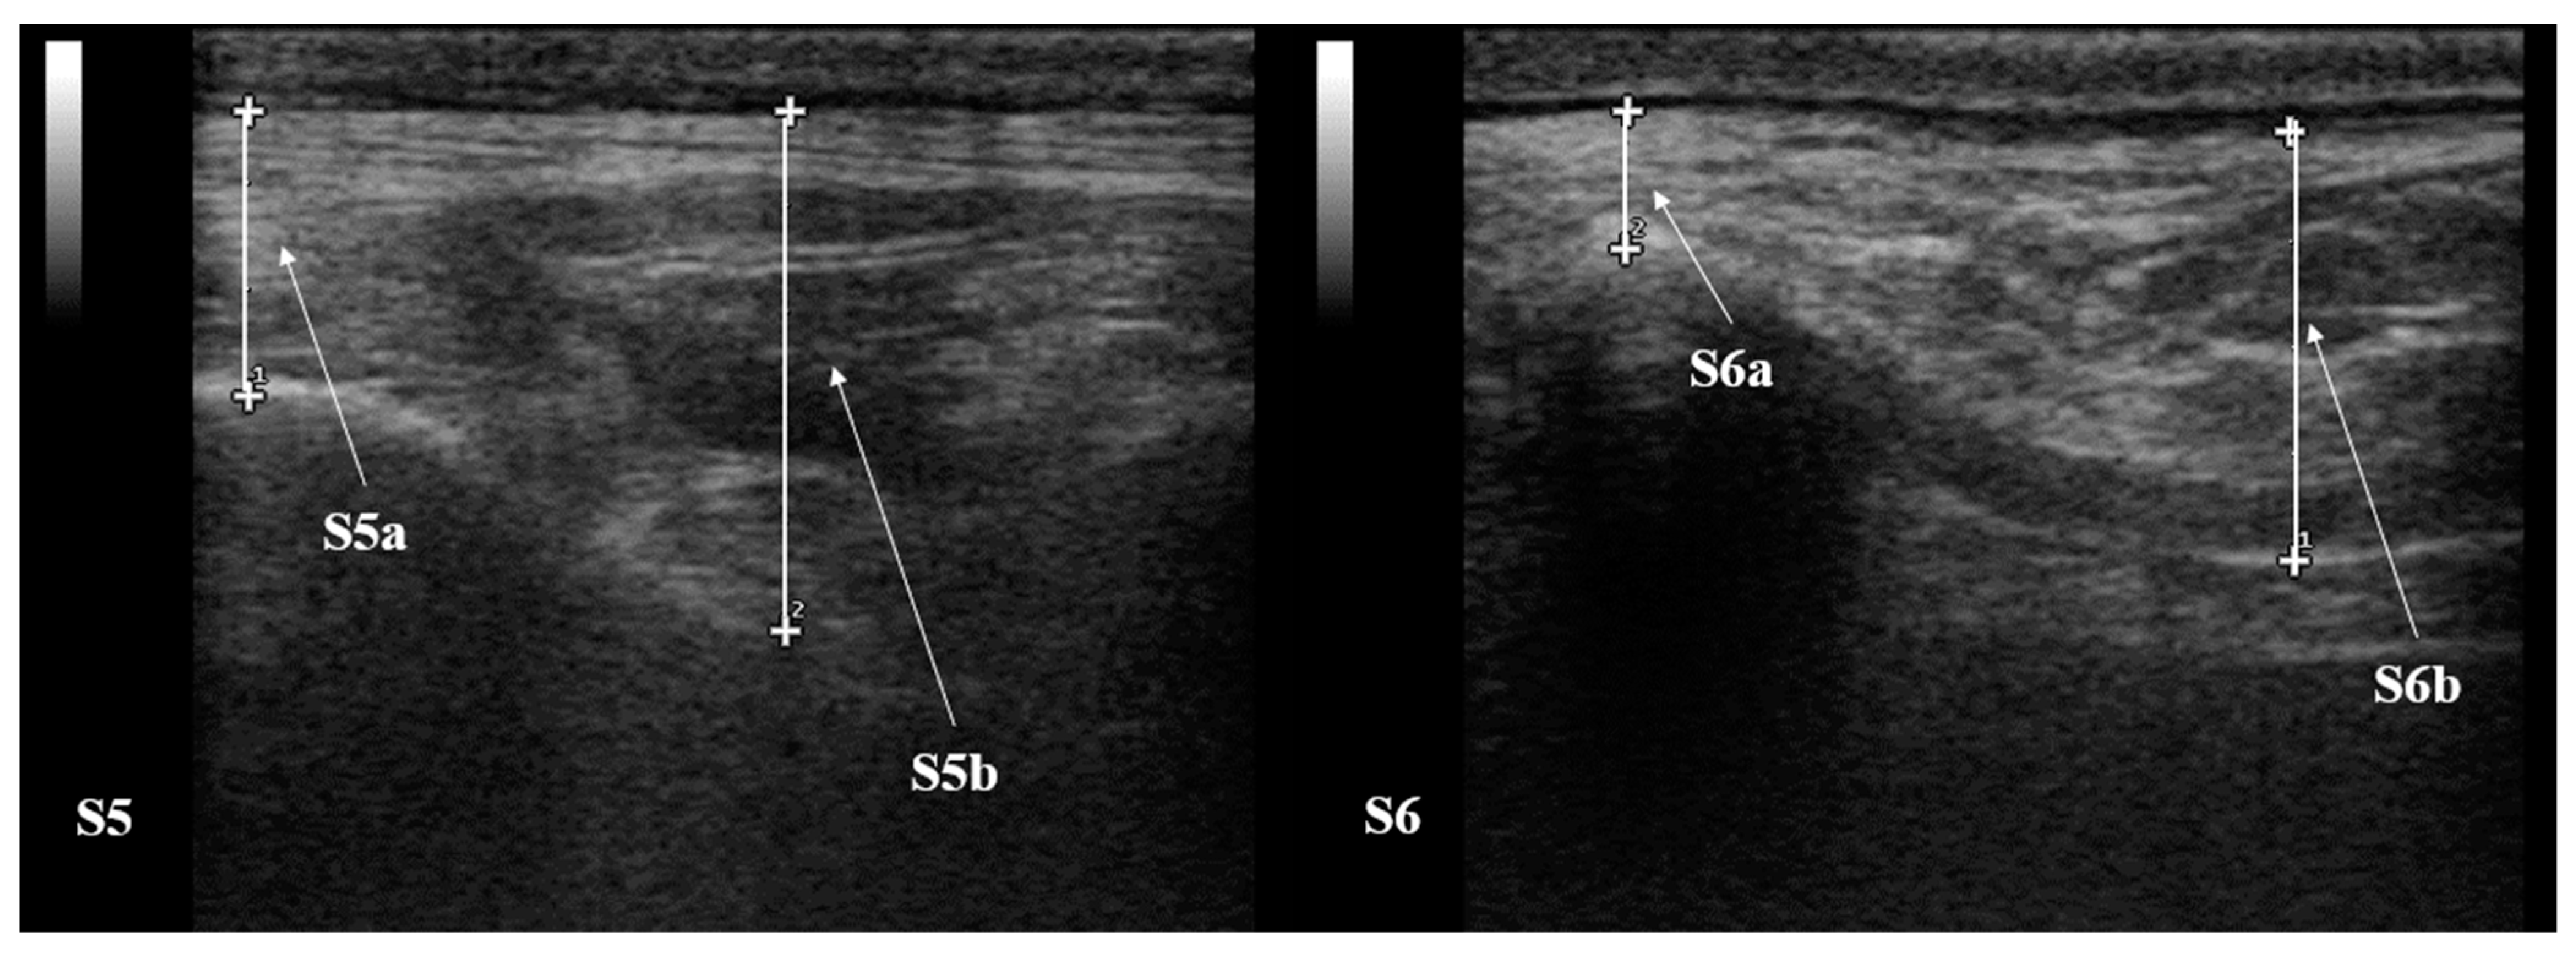

| S5 (mm) | a | 10.25 ± 2.86 | 11.17 ± 3.19 | 10.70 ± 4.17 | 10.02 ± 3.37 | 9.17 ± 3.82 |

| b | 20.83 ± 13.51 | 20.18 ± 1.49 | 17.78 ± 4.30 | 21.15 ± 2.10 | 18.92 ± 4.58 | |

| S6 (mm) | a | 10.55 ± 3.12 | 8.53 ± 2.38 | 8.47 ± 3.00 | 6.25 ± 2.76 | 4.72 ± 2.60 |

| b | 20.28 ± 4.32 | 18.10 ± 2.42 | 20.17 ± 3.70 | 16.50 ± 3.56 | 17.58 ± 4.15 | |